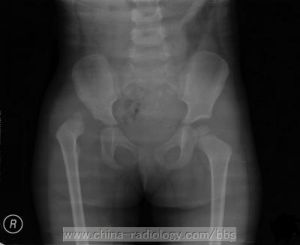

6.X線檢查 對疑有先天性髖關節脫位的患者,應在出生後3個月以上(在此之前髖臼大部分還是軟骨)拍雙側髖關節的骨盆正位片。X線片上可發現髖臼發育不良,板半脫位或脫位。拍攝X線片時,應加性腺防護板。

(1)髖臼角測定:髖關節的發育狀況常用髖臼角的傾斜度來測定。通過雙側髖臼軟骨(亦稱Y形軟骨)中心點連一直線並加以延長,稱Y線。再從Y線軟骨中心點向骨性髖臼頂部外側上緣最突出點連一條線,此線稱C線。C線與Y線的夾角即為髖臼角或叫做髖臼指數。正常新生兒為30°-40°,1歲23°-28°,3歲20°-25°。大於此範圍者表示髖臼發育不全,說明此髖臼窩較淺,即使股骨頭的骨化中心在髖臼內,以後仍有可能發生脫位。

(2)股骨頭的位置及關節四區劃分法 Shenton線(股骨頸與閉孔連線)測量法:正常情況下,閉孔上緣和股骨頸內側緣可連成弧形曲線。當髖關節脫位後此線不能連成完整的弧線,也稱為Shinton線中斷。關節四區劃分法:由髖臼外上緣向Y線作一垂直線,將髖臼分為四個區。正常情況下,股骨頭的骨化中心在內下區內。如不在此區內,依程度不同可分為半脫位或脫位。

h-f測量法:新生兒和嬰兒時股骨頭骨骺未出現,此時可用測量h和f的方法來觀察。h為股骨頸部上端外側與Y線的垂直距離。f為股骨頸上端內側處(A點)向Y線引一平行線,此線向內側與坐骨支的相交點為B點。A和B之間距離為f。當脫臼時,h變小,f增大。

VonRosen拍片法:雙側下肢伸直外展45°,髖關節內鏇位拍片。正常情況下股骨幹中軸線向上延長,此線通過髖臼內側。半脫位、脫位時此線通過髖臼外側。

(3)股骨頭骨化中心較健側小。因發育受到影響所致。

(4)患側股骨頸前傾角大,正位X線片上股骨頸越短、粗,則前傾角越大。